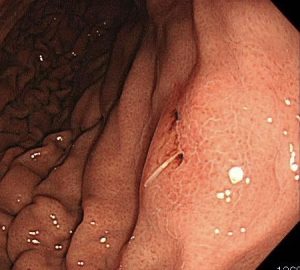

鉗子で除去していきます。

無事に捕獲。